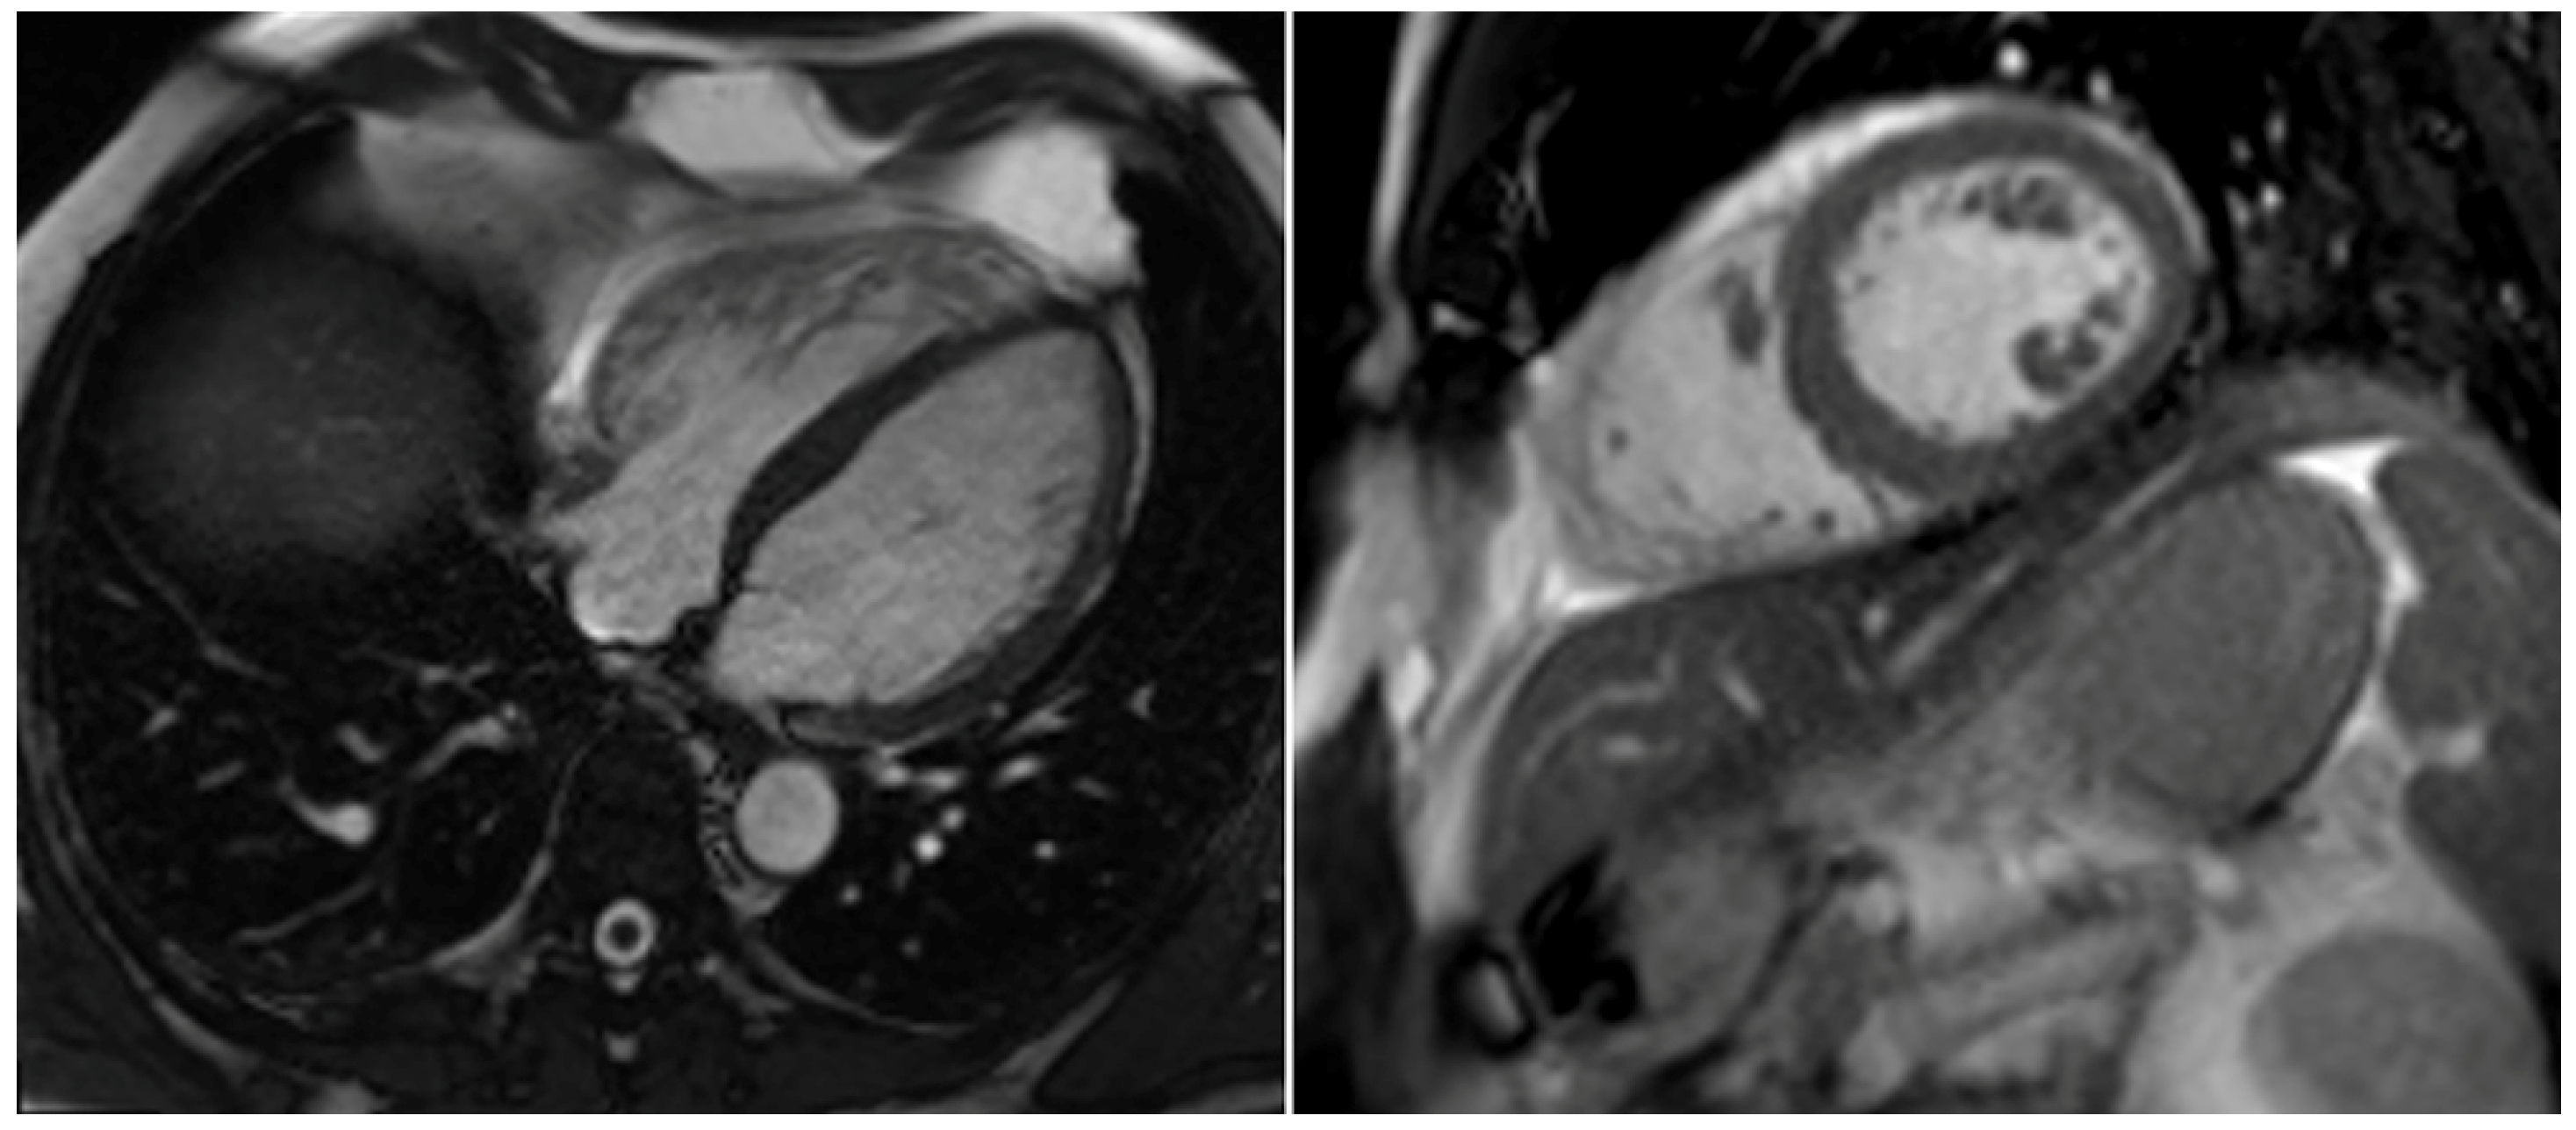

2. Case Report

| RVEDD [mm] | 65 | 49 | 37 |

| LVEF [%] | 43 | 54 | 56 |